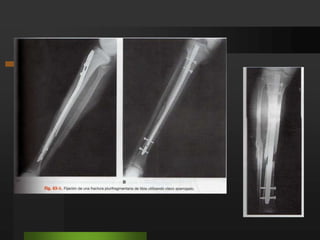

OsteosíntesisFRACTURAS DE LA PIERNAImplantes intramedularesImplantes rígidos.

Clavo intramedular de Küntscher. (más utilizado)

Clavo acerrojado.

Trabas proximales o distales con tornillos pasados en forma perpendicular al clavo.

OsteosíntesisFRACTURAS DE LAPIERNAImplantes intramedularesImplantes rígidos.

Clavo intramedular deKüntscher. (más utilizado)

Trabas proximales odistales con tornillos pasados en forma perpendicular al clavo.